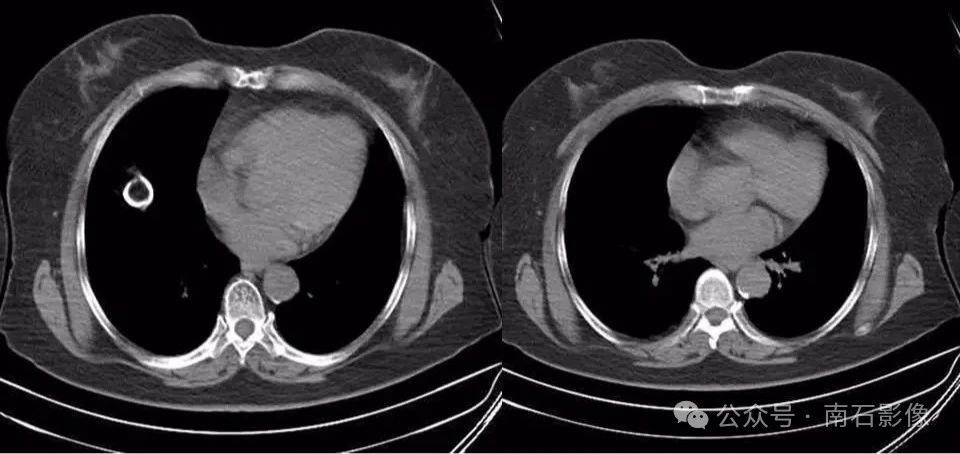

7.肝脏血色病,铁过量沉积引起肝脏弥漫性密度增高,“白肝”。

07217b02b6afc6893293444a5d45707f.jpg